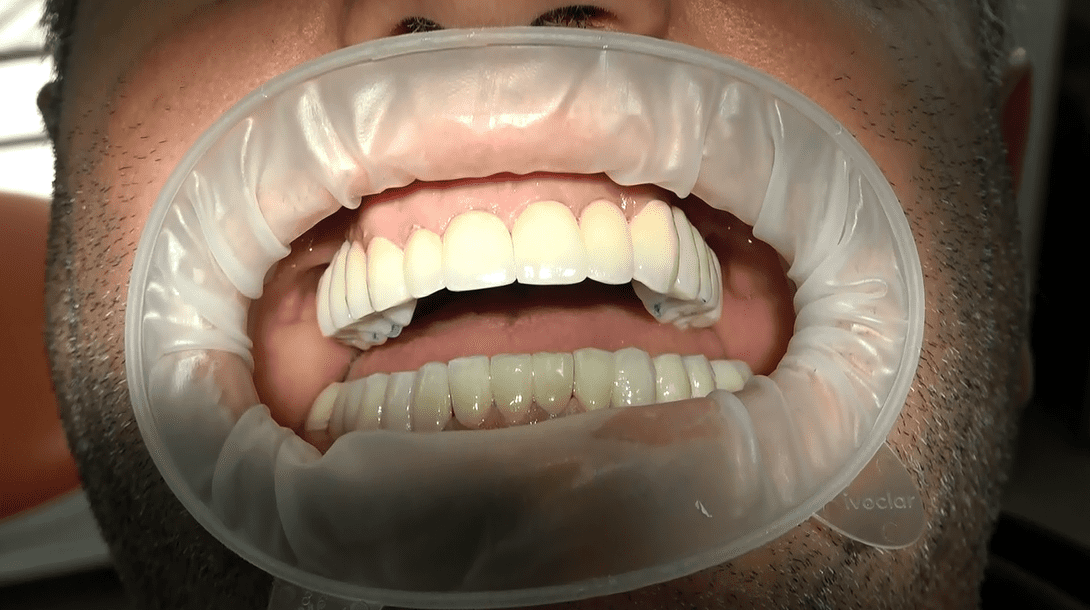

Ulteriore caso clinico

Prima dell’intervento implantare, affrontiamo le atrofie e le zone problematiche attraverso interventi preventivi. Il nostro obiettivo è ottenere non solo una funzione masticatoria ottimale ma anche una soluzione estetica preventivata con il paziente. Garantiamo circolari fissi in ceramica senza falsa gengiva, con elementi dentali che emergono naturalmente senza aggiunte antiestetiche.

La stretta collaborazione tra implantologo e protesista è essenziale per garantire un risultato estetico garantito. Ogni passo del processo è sincronizzato per creare un sorriso che rispecchi le aspettative estetiche e funzionali del paziente.